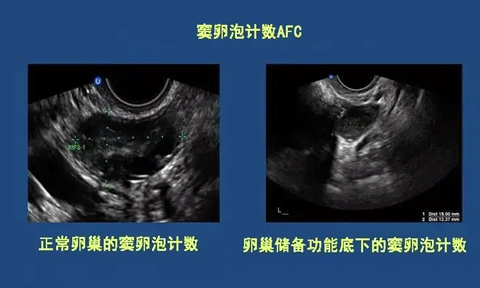

女性在进行窦卵泡计数检查时,常常会对“窦卵泡计数”这一概念感到困惑。简单来说,窦卵泡是指卵巢内发育的最原始的三级卵泡。通过阴道超声或彩超技术,可以有效地进行窦卵泡计数,从而准确评估其数量。由于女性的生育能力会随着时间而变化,因此窦卵泡计数在医学上被认为是评估卵巢储备功能的最佳方法。此外,在进行试管婴儿手术时,也需要根据这种计数来判断卵巢对药物的反应,从而提高成功率。窦卵泡计数的目的在于计算出基础卵泡的数量,以便获得所需的结果。

经过对窦卵泡计数的准确分析,结果并不总是令人满意。在正常情况下,卵巢的卵泡数量应在5到10个之间。如果卵泡数量超过10个,可能会怀疑存在多囊卵巢的问题;而如果少于5个,则可能是卵巢功能减退所致。